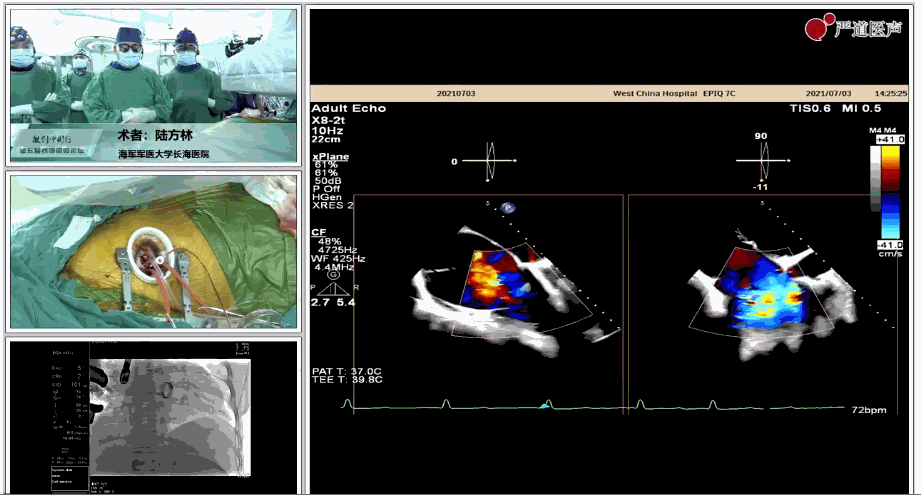

7月3日下午,海軍軍醫(yī)大學(xué)附屬上海長(zhǎng)海醫(yī)院心血管外科徐志云、陸方林團(tuán)隊(duì)在論壇中分享了經(jīng)導(dǎo)管三尖瓣置換術(shù)(LuX-Valve®)的手術(shù)直播演示。線下會(huì)議由陶涼教授、潘文志教授、喬晨暉教授共同參與討論和臨床分享。

陸方林教授分享的是一例極重度三尖瓣返流的患者采用健世科技(LuX-Valve®)經(jīng)導(dǎo)管三尖瓣置換系統(tǒng)進(jìn)行的手術(shù)直播演示。此例患者為69歲女性,入院前17年行二尖瓣機(jī)械瓣置換術(shù),術(shù)后長(zhǎng)期服用華法林抗凝,既往“2型糖尿病”病史5年,“雙下肢水腫”3年。3個(gè)月前患者出現(xiàn)腹脹、雙下肢水腫,伴活動(dòng)后暈厥,伴黃疽、皮膚濕癢、牙齦出血,癥狀持續(xù)加重,遂入院治療。入院后行心臟CT、心臟超聲檢查,提示:“三尖瓣關(guān)閉不全(極重度),二尖瓣置換術(shù)后,心功能III級(jí)”。徐志云、陸方林微創(chuàng)三尖瓣置換團(tuán)隊(duì)對(duì)該患者的病情進(jìn)行了充分的評(píng)估和討論。由于患者有開胸二尖瓣置換手術(shù)史,且病史時(shí)間長(zhǎng),同時(shí)存在相關(guān)合并癥,傳統(tǒng)外科手術(shù)風(fēng)險(xiǎn)極高(STS評(píng)分:8.315%),最終決定采用三尖瓣LuX-Valve®瓣膜系統(tǒng)對(duì)患者進(jìn)行治療。

圖片

▲瓣膜植入前右心室造影

在手術(shù)直播中瓣膜植入過程不到10分鐘,手術(shù)獲得圓滿成功,充分體現(xiàn)徐志云、陸方林團(tuán)隊(duì)技術(shù)精湛,團(tuán)隊(duì)協(xié)作默契及器械的優(yōu)越性。

該例患者返回后當(dāng)天拔除氣管插管,生命體征穩(wěn)定,恢復(fù)良好。此次會(huì)議不僅有最前沿的學(xué)術(shù)講座,更有3D體驗(yàn)般的手術(shù)直播,為大家第一視角直觀呈現(xiàn)領(lǐng)域新技術(shù)、新策略、新思路。